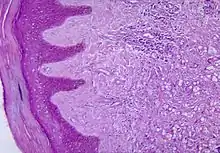

| Histopathological changes in the skin seen in lobomycosis. Source: CDC | |

Diagnosis of Lobo's disease is made by taking a sample of the infected skin (a skin biopsy) and examining it under the microscope. Lacazia loboi is characterized by long chains of spherical cells interconnected by tubules. The cells appear to be yeast-like with a diameter of 5 to 12 μm. Attempts to culture L. loboi have so far been unsuccessful.[10]